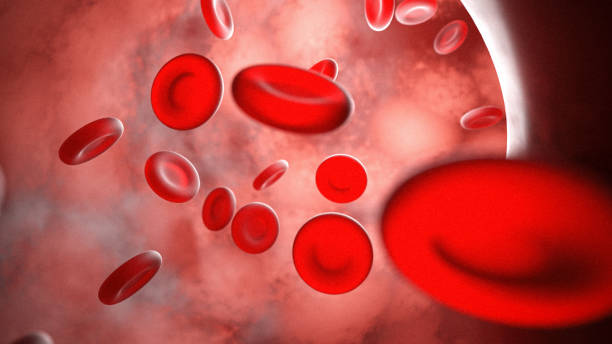

Een goede doorbloeding is cruciaal voor het lichaam om voedingsstoffen en zuurstof efficiënt te kunnen transporteren en goed te laten functioneren. Helaas kunnen er soms blokkades ontstaan in de bloedcirculatie, waardoor belangrijke lichaamsdelen een tekort aan zuurstof kunnen krijgen. Het is daarom van groot belang om snel in te grijpen bij dergelijke situaties, zodat de balans hersteld kan worden en het lichaam optimaal blijft functioneren en zich goed blijft voelen.

Veranderingen in de bloedcirculatie, die kunnen worden veroorzaakt door verschillende factoren zoals stress, lichamelijke inspanning of medicatiegebruik, kunnen tijdelijk leiden tot een verhoogde druk in de hersenen, wat vervolgens kan resulteren in intense spanning en hevige hoofdpijn bij individuen.

Een nauwkeurige en effectieve samenwerking tussen de ogen, evenwichtsorganen en hersenen is essentieel voor het lichaam om een stabiel beeld van de omgeving te behouden, zodat we ons kunnen oriënteren en bewegen. Echter, tijdelijke veranderingen in de bloedcirculatie, zoals stress of vermoeidheid, kunnen deze samenwerking verstoren en ons gevoel van balans en ruimte negatief beïnvloeden.

De hersenen spelen een cruciale rol bij het verwerken van visuele informatie en het coördineren van bewegingen, aangezien zij verantwoordelijk zijn voor het interpreteren van visuele signalen en het aansturen van spieractiviteit. Echter, een tijdelijke verandering in de bloedtoevoer naar de hersenen kan leiden tot tijdelijke verstoringen in het evenwicht en het zicht van een persoon, waardoor zij bijvoorbeeld duizelig kunnen worden of moeite kunnen hebben met scherp zien.